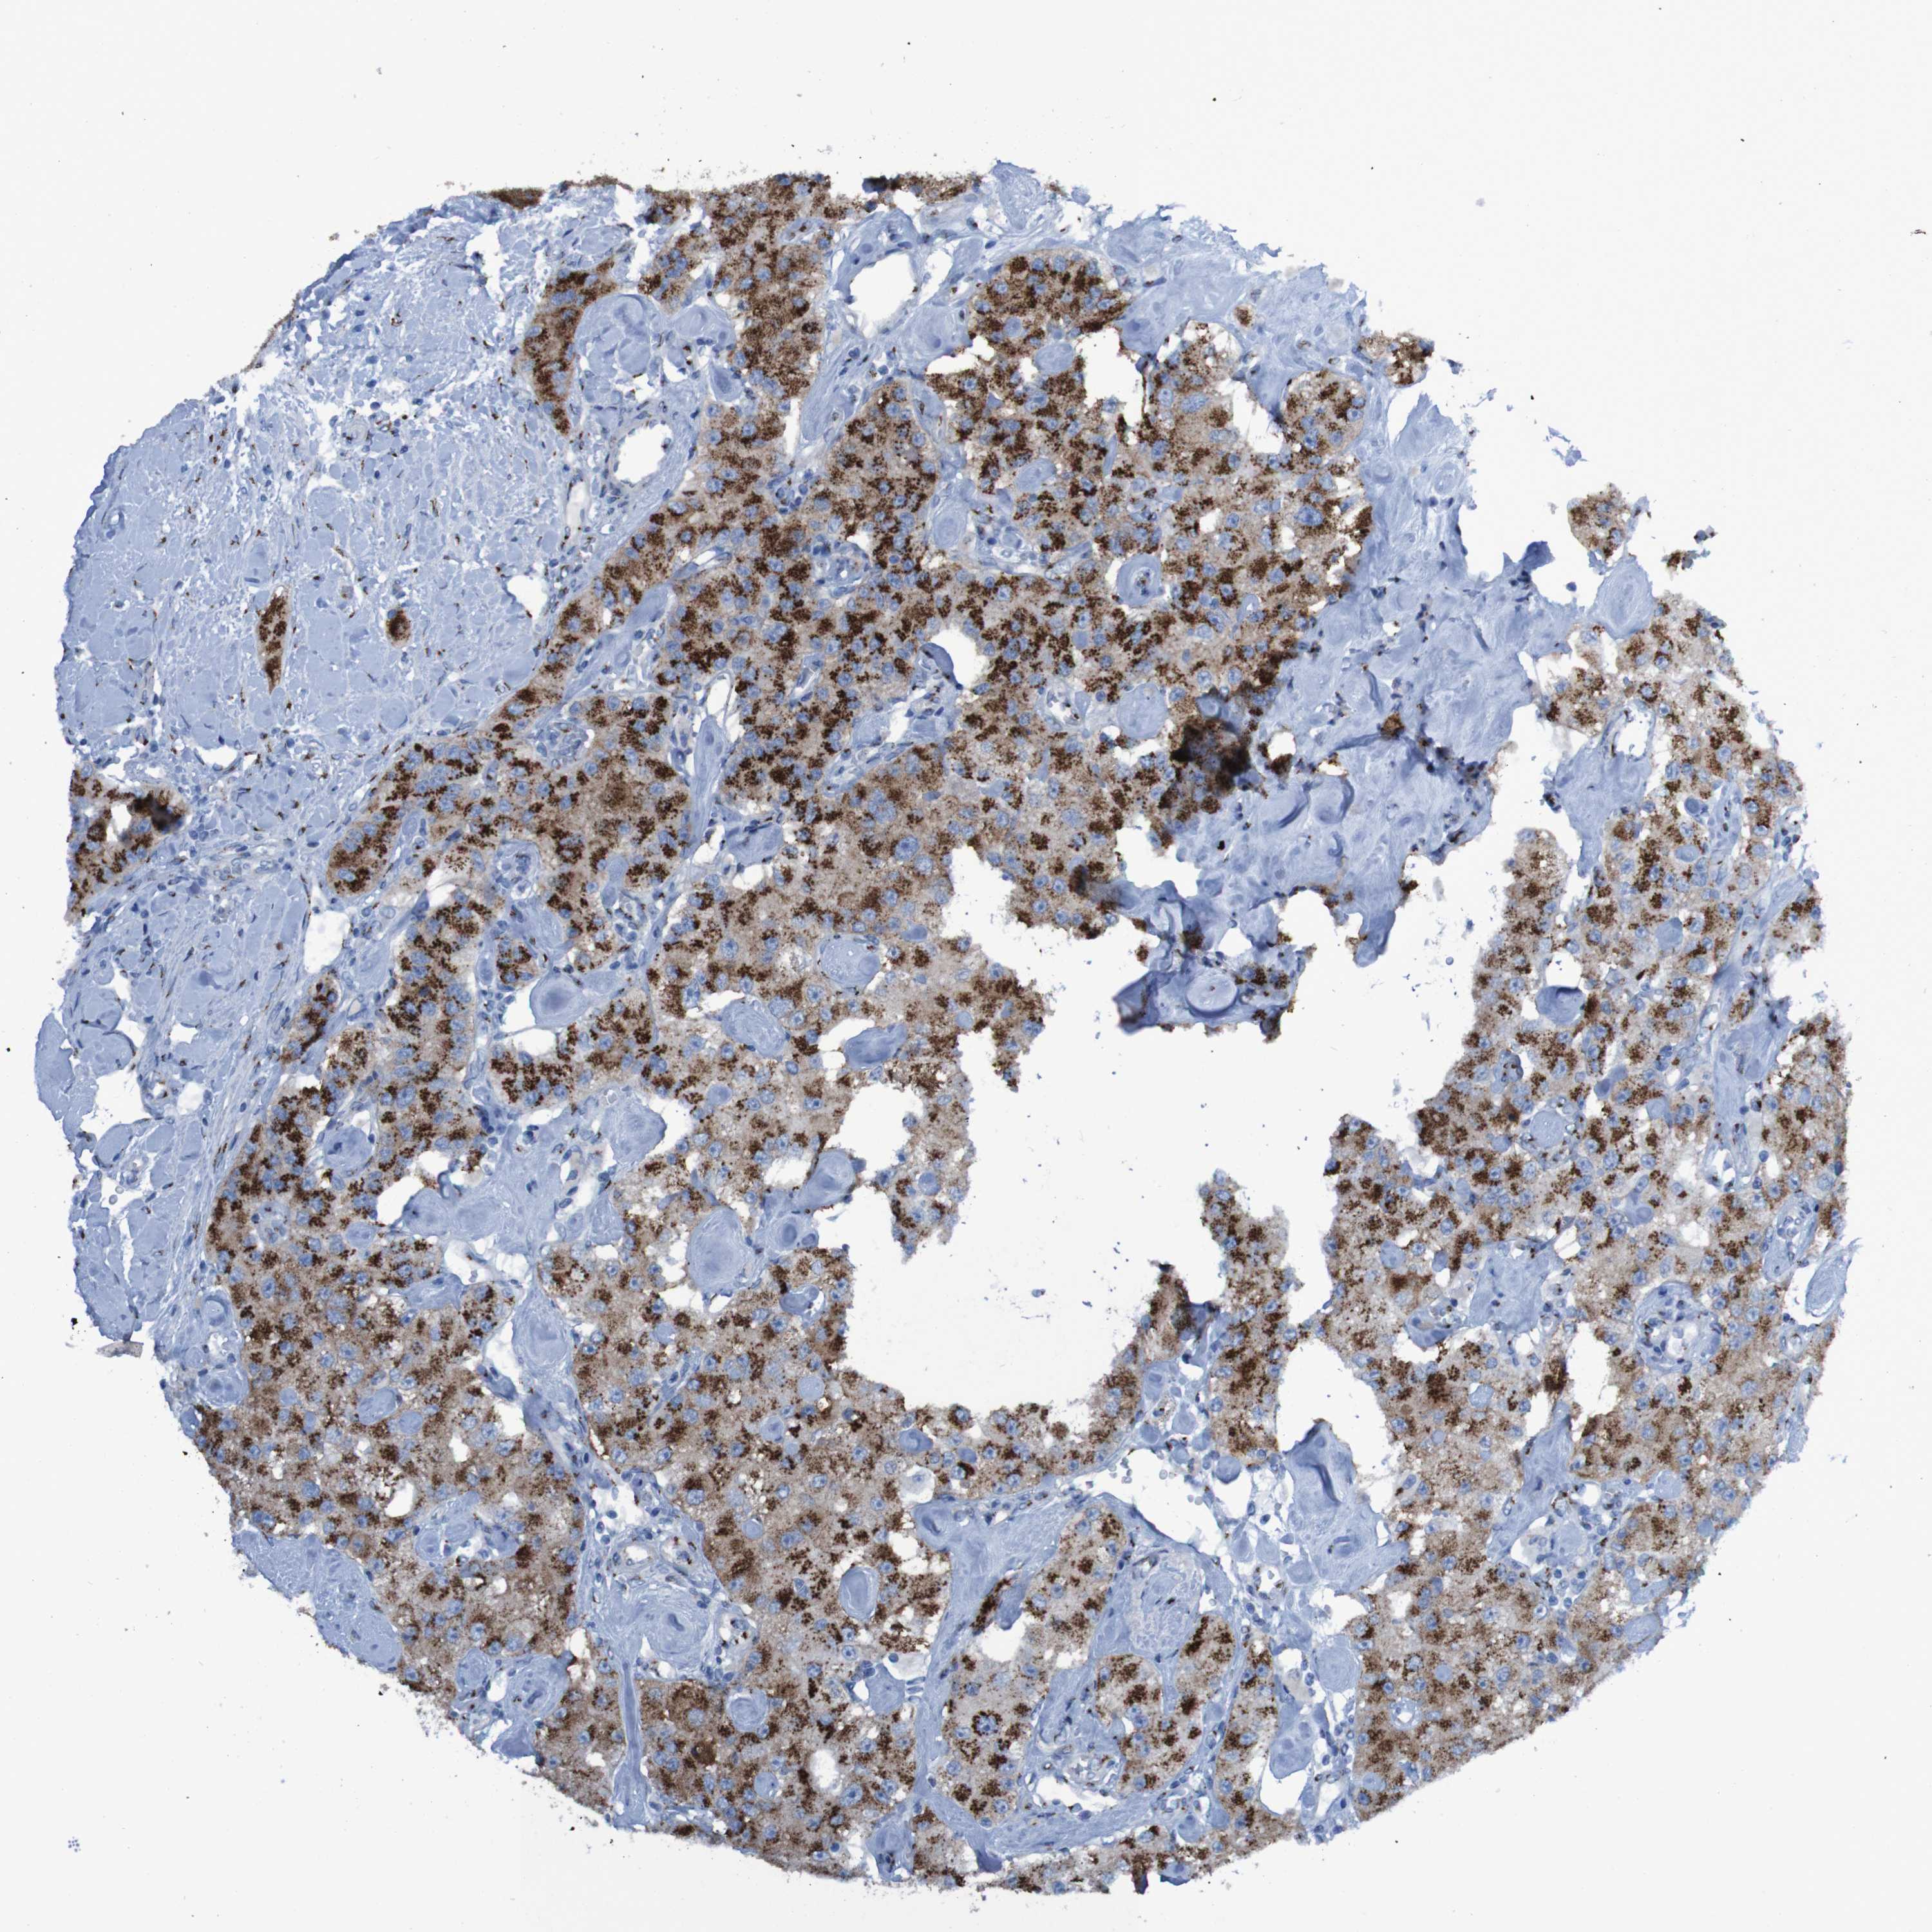

CARCINOID - Protein expressioni

A mouse-over function shows sample information and annotation data. Click on an image to view it in a full screen mode. Samples can be filtered based on level of antibody staining by selecting one or several of the following categories: high, medium, low and not detected. The assay and annotation is described here.

Antibody stainingi

Antibody staining in the annotated cell types in the current human tissue is reported as not detected, low, medium, or high, based on conventional immunohistochemistry profiling in selected tissues. This score is based on the combination of the staining intensity and fraction of stained cells.

Each image is clickable and will lead to virtual microscopy that enables deeper exploration of all samples and also displays staining intensity scores, fraction scores and subcellular localization as well as patient and tissue information for each sample.

Antibody HPA011929

Staining

High

Strong

>75%

Cytoplasmic/membranous

Carcinoid, malignant, NOS